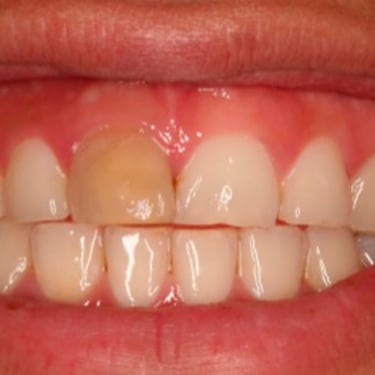

Lesión Traumática Pulpar

Una lesión traumática pulpar es un daño a la pulpa dental debido a un trauma, como un golpe en el diente.

Los pacientes pueden experimentar dolor, sensibilidad y decoloración del diente.

El tratamiento incluye evaluar la vitalidad de la pulpa y, si es necesario, realizar un tratamiento de conducto. Es importante tratar la lesión para evitar complicaciones a largo plazo.